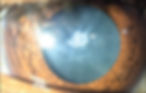

A catarata é uma doença ocular que ocorre quando o cristalino, uma lente natural do olho, se torna opaco. O cristalino é responsável por focar a luz na retina, que é a parte do olho que converte a luz em imagens. Quando o cristalino fica opaco, a luz não consegue passar corretamente e a visão fica prejudicada.